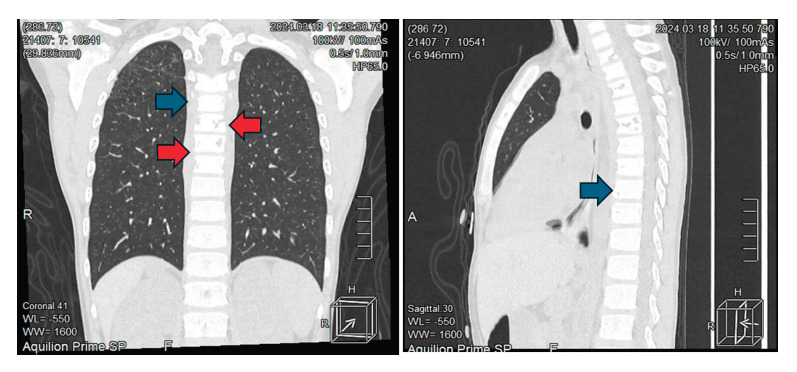

Primary adrenal insufficiency is the result of impaired steroid synthesis, adrenal destruction or abnormal development of the adrenal gland affecting the adrenal cortex. Tuberculosis is one of the main causes in developing countries. We present the case of a 10-year-old male patient diagnosed with adrenal insufficiency two years earlier with regular treatment, who was admitted for adrenal crisis. A thoraco-abdominal tomography was carried out during hospitalization, which showed cylindrical and traction bronchiectasis associated with cicatricial atelectasis in the right upper pulmonary lobe, enlarged adrenal glands with foci of calcification, as well as a dense posterior perivertebral mediastinal collection also involving vertebral bodies with lytic resorptive foci, findings consistent with systemic tuberculosis. Treatment for tuberculosis started based on this diagnosis. During course of the disease, the first phase was completed with four drugs, and the second phase included isoniazid and rifampicin with favorable clinical response.